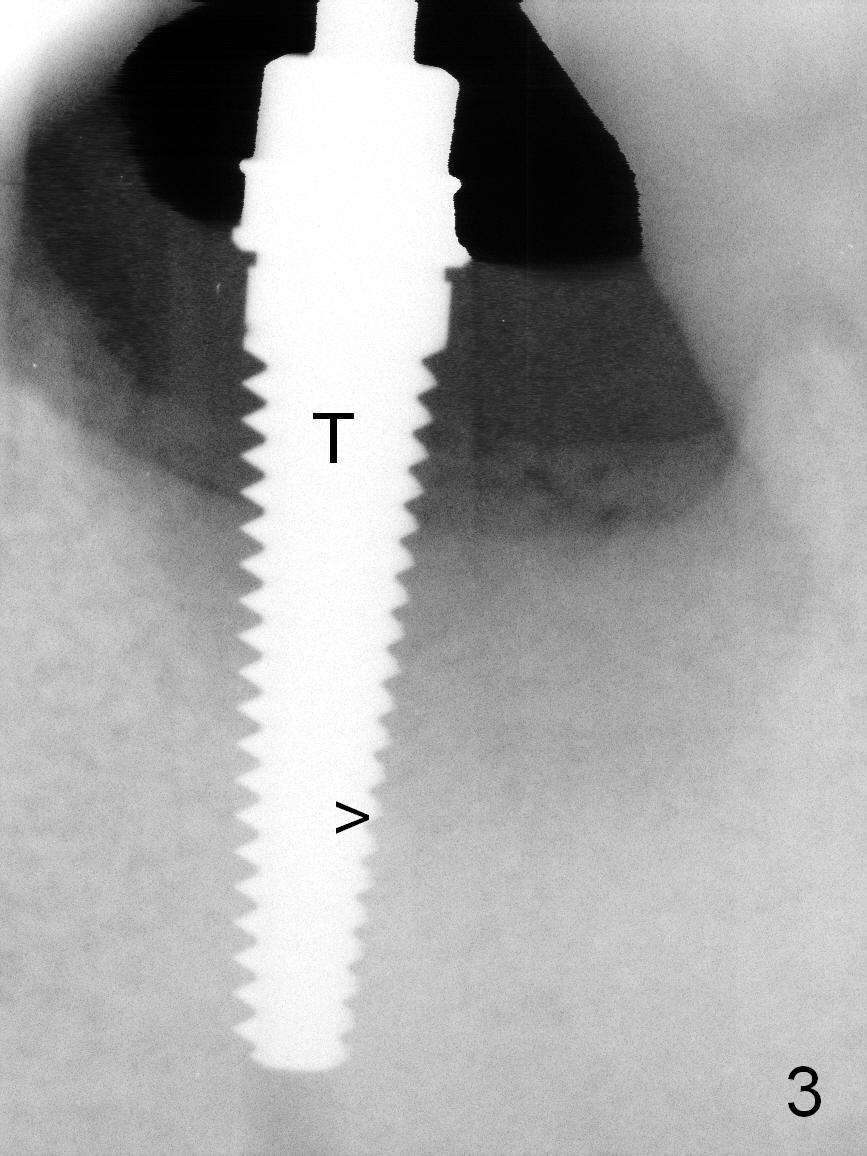

When the patient returns for #19 extraction and immediate implant, there is buccal (Fig.1 *) and lingual gingival swelling. The distobuccal root is exposed (D). Both the buccal and lingual walls are low. There is no septum. After removal of granulation tissue, an osteotomy is established in the bottom of the socket (slightly mesiolingually). The depth is approximately 3 mm in new bone (half of 6 mm and arrowhead). When the depth increases approximately 6 mm in new bone (Fig.3 arrowhead with 6x20 mm tap (T) in place), the Inferior Alveolar Canal is still invisible in PA. Panoramic X-ray has to be taken (Fig.4). So far infiltration anesthesia has been administered. When #2 sensor is inserted in the lingual vestibule, the patient feels pain and nausea. Lingual Nerve block is provided. The patient feels pain when further osteotomy is carried on. Since the depth of the osteotomy is confirmed by panoramic X-ray, Inferior Alveolar Nerve block is added. A 6x17 mm tissue-level implant is placed with clearance from the Inferior Alveolar Canal (Fig.5: red dashed line: the superior border of the Canal). Therefore, Lingual Nerve block allows lower placement of sensor so that the Inferior Alveolar Canal is detectable by PA.